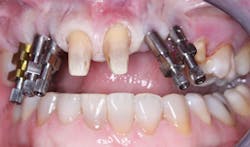

Observe Figs. 5-10 for a classic example of when crowns cannot be screwed onto abutments. The patient did not want to have bone grafting, and the implants were placed where there was minimally adequate bone. These implants were placed by a very competent periodontist. The significant angulation of the implants from the optimum angulation is easily observed with the impression copings on the implant bodies in Fig. 6. Custom abutments were mandatory, as shown in Fig. 6. The resultant crowns (Figs. 9-10) created a very acceptable esthetic result. It is very obvious that if crowns had been screwed onto the implants without an abutment, the screw entry would have been through the facial or incisal portion of the crowns.

FIG. 7 -- An open impression tray was required because of the severely nonparallel placement of the implants.

FIG. 8 -- Custom abutments were required for this patient because of the implant placement angulation.